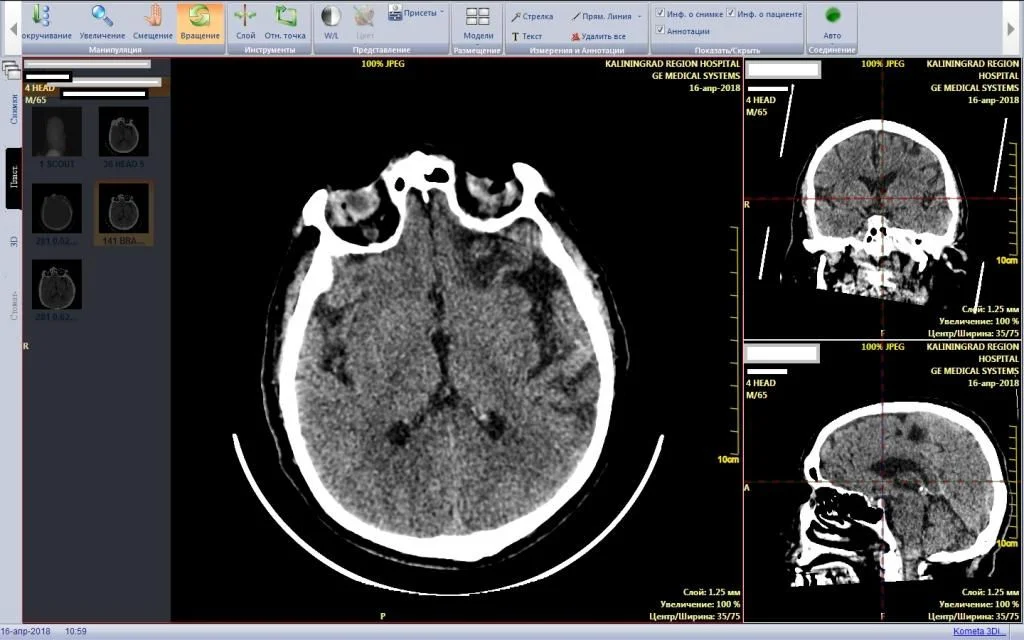

Информационная система обмена медицинскими изображениями с центральным архивом медицинских изображений

Для повышения качества и оперативности предоставления медицинских услуг путем автоматизации процессов в области лучевой диагностики, автоматизации функций хранения, передачи, обмена, интерпретации и консультирования медицинских изображений в рамках единого информационного пространства на территории Калининградской области был развернут Центральный архив медицинских изображений (ЦАМИ) и информационная система обработки медицинских изображений (ИСОМИ) на основе программного обеспечения Kometa 3Di PACS.

- автоматизация процессов проведения диагностических исследований с использованием цифрового оборудования лучевой диагностики, поддерживающего стандарт создания, хранения, передачи и визуализации медицинских изображений и документов обследованных пациентов DICOM; - ЦАМИ является долговременным хранилищем цифровых медицинских изображений, используется для сбора медицинских изображений и маршрутизации результатов исследований между медицинскими организациями для оперативного принятия решений по оказанию экстренной медицинской помощи или при выходе из строя оборудования в каком-либо из районов;

- ЦАМИ/ИСОМИ интегрированы с медицинской информационной системой «БАРС.Здравоохранение» (МИС) и региональной электронной медицинской картой пациента (ЭМК).

-         ИСОМИ поддерживает стандарт визуализации медицинских изображений и документов и предоставляет по протоколу HTML5 доступ к медицинским изображениям из ЭМК МИС, а также, используется для работы главных внештатных специалистов и экспертов министерства здравоохранения Калининградской области;

Мультипланарная реконструкция КТ исследования